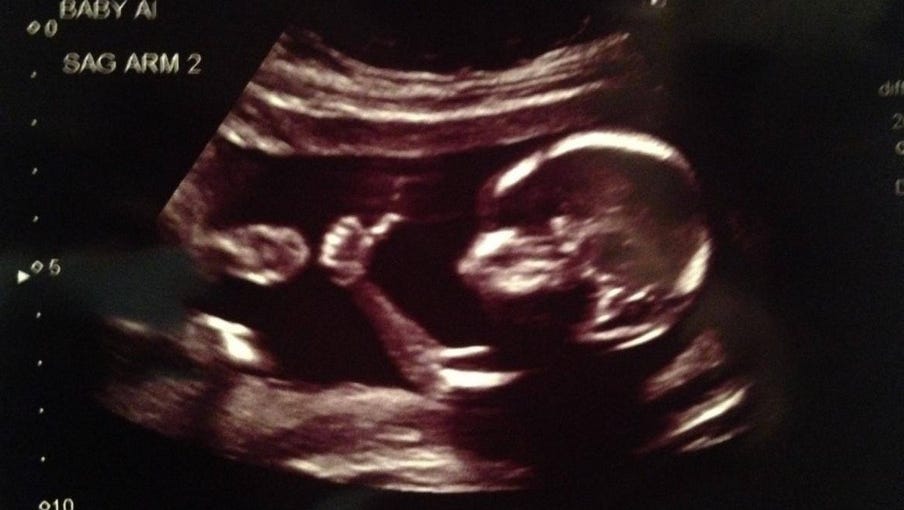

Baby Gives Thumbs Up In Ultrasound Photo